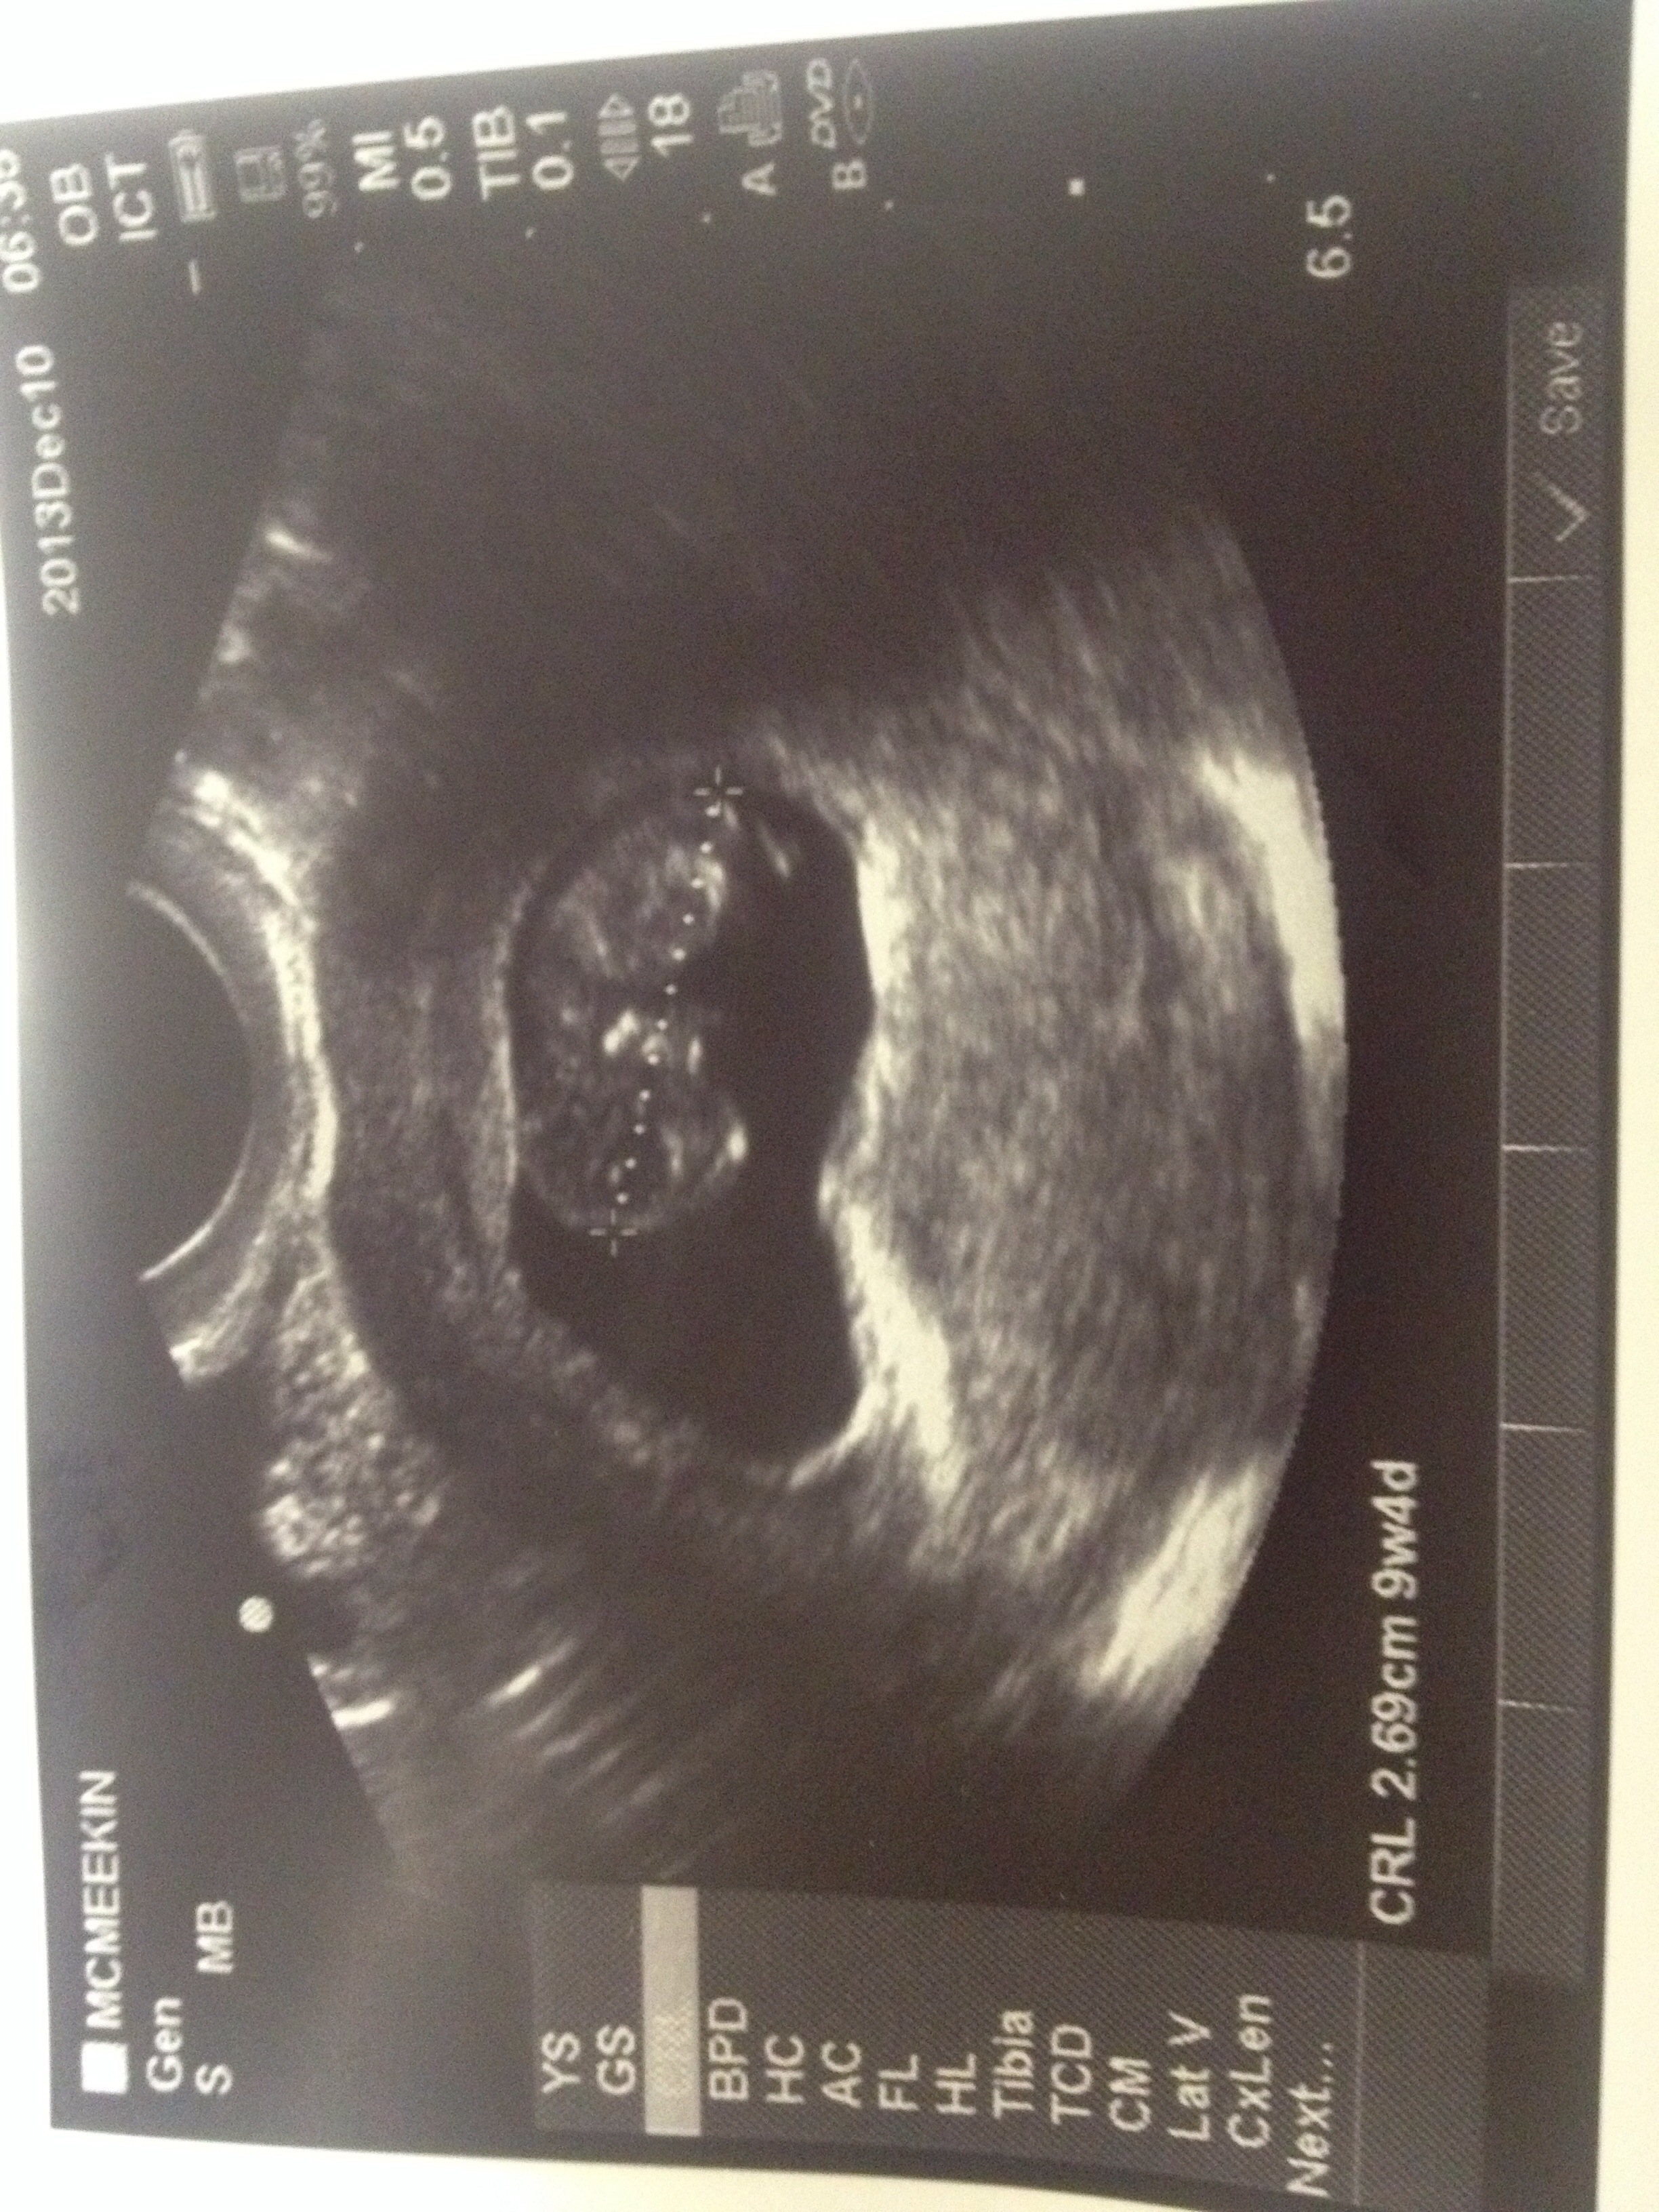

The worst year of my life is over. A new year has begun and I find myself in a very similar position that I was this time last year: pregnant. 13 and a half weeks pregnant to be exact. Over the moon happy, and more scared than I have ever been in my life.

I have been avoiding my blog since I found out, because I have been so scared to openly admit to the world (and myself) that Everlee’s little brother or sister is nestled quietly in my belly. But with a new year comes new hope. After every great storm, there is a rainbow. I am so grateful to be pregnant with my rainbow baby.

2014 will bring many doctors appointments, lots of bed rest, a lot of anxiety and hopefully in June, a little healthy and alive brother or sister for my darling little girl.